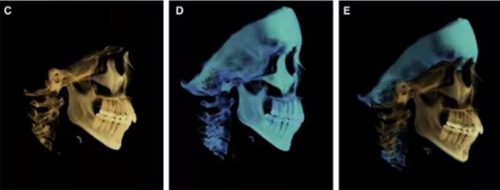

頭側(cè)分析提示為骨性安氏II類(lèi)(ANB,8.4°;Wits,3.6mm),高角(SN-MP,44.9°),上頜切牙略舌傾(U1-SN,96.2°),下頜切牙略舌傾(IMPA,88。3°)(圖2;表)

治療后頭側(cè)數(shù)據(jù)提示:無(wú)明顯骨性變化(上頜SNA82.1°,下頜SNB74.9°),上頜前牙得到內(nèi)收,略舌傾,頦部前后位置無(wú)明顯改變,仍未凸面型(圖8,表)。將治療前后圖像重疊后結(jié)果如(圖8及圖9),24月后隨訪結(jié)果見(jiàn)圖10.